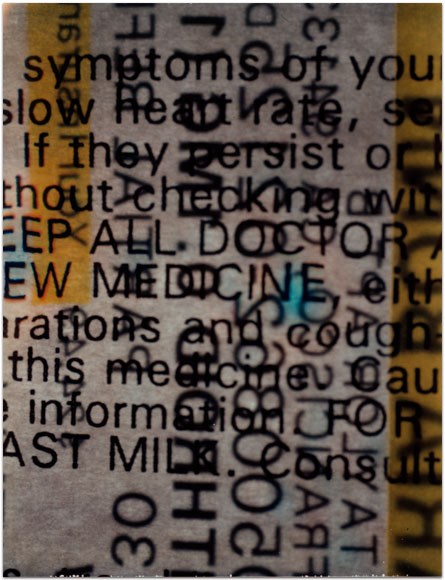

- Itis

- 2004

- 3.25″ × 4.25″

- Photographic montages of my hands & health paraphernalia on Polaroid Type 664 & 669 Film using a Daylab Printer.

- Frustrated by a lack of mobility and severe pain with my fingers, unable to accomplish any task requiring joint dexterity,

I noticed piles of health related papers strewn around. I layered these in a slide printer without removing

my hands, enlarging both onto the film.